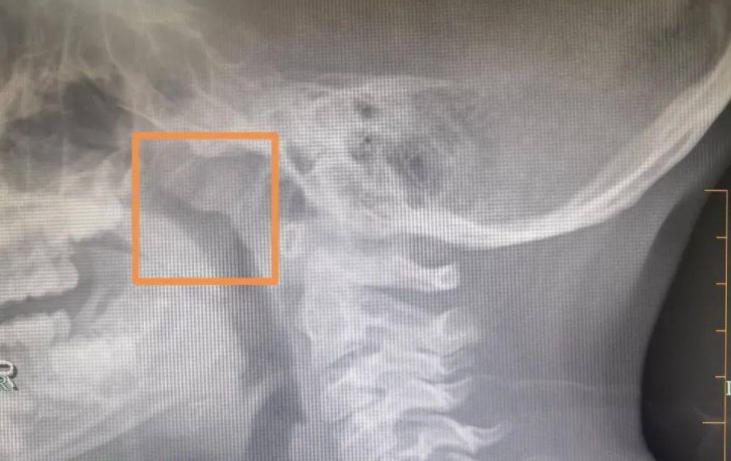

另一種表現是耳後持續腫脹或硬塊,這個位置從醫學上來說,靠近淋巴系統。如果這個區域長時間摸到硬結,按壓不疼,也不消退,尤其是幾周甚至更久,那就必須警覺。因為有些頭頸部腫瘤,最早就是從這裡「打前站」。

耳朵是頭頸部腫瘤早期的「前哨」之一。比如鼻咽癌、口腔癌、喉癌,甚至一些淋巴瘤,它們在早期階段,常常會幹擾耳道壓力、影響聽覺神經、牽動附近淋巴結。耳朵先出事,是有跡可循的,並非偶然。

(圖為示意圖/ENT Specialists Of Northern Virginia)

更隱蔽的是,癌細胞會通過血液或淋巴傳播,最早在耳後淋巴結現身。這些地方不像頸部那樣容易引起注意,所以很多人根本不會去摸,也不會想到它出了問題。

耳朵問題的「時間跨度」尤其關鍵。如果你發現自己耳鳴超過兩周,或者耳後腫塊超過一個月不消,即使沒有其他症狀,也該去檢查。不是去挖耳朵,而是做一個鼻咽、頸部的影像學檢查,可能更有意義。